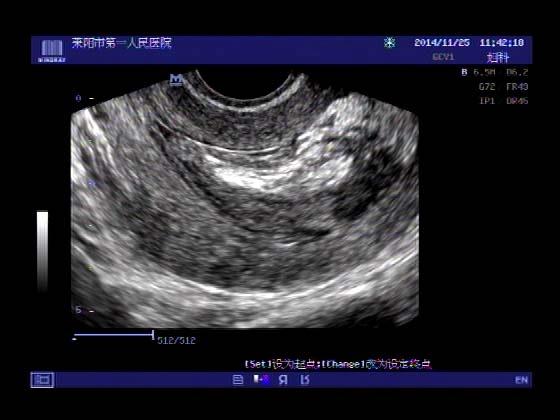

超声入门贴379---------粘膜下肌瘤(阴超的魅力)

女,43岁,月经量多3个多月,加重一个月

外院彩超检查提示:子宫后肌壁略高回声团------肌瘤?息肉?,盆腔少量积液

今天来我院检查:

巧妇难为无米之炊,经腹部超声确实很难定,阴超一目了然,乡镇医院诊断水平的提高更迫切的需要高档仪器的引进!